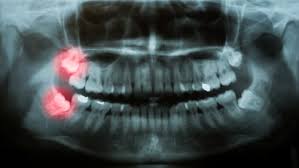

Would it help if the dentist cuts away the remaining gum that's covering the tooth!?!?! For example, if you are one of the unlucky few who have impacted wisdom teeth, you may have to wait till your early 20s before the dentist is able to extract the teeth from the. In america if your wisdoms don't erupt by 21 they take them out, whether they're causing problems or not! Impacted wisdom teeth that grow horizontally happens due to spacing issues within your mouth. Wisdom teeth that fully grow in above the gum line don't usually cause much pain or swelling beyond a few weeks.

Wisdom Teeth Extractions Third Molars Are Often Impacted

Wisdom Teeth Extractions Third Molars Are Often Impacted from www.lowelloralsurgery.com

When Should I Extract Impacted Wisdom Teeth Woodbridge Dentists

When Should I Extract Impacted Wisdom Teeth Woodbridge Dentists from lifetimedentalcareva.com

Wisdom teeth that do not have enough room to grow properly are known as impacted wisdom teeth.